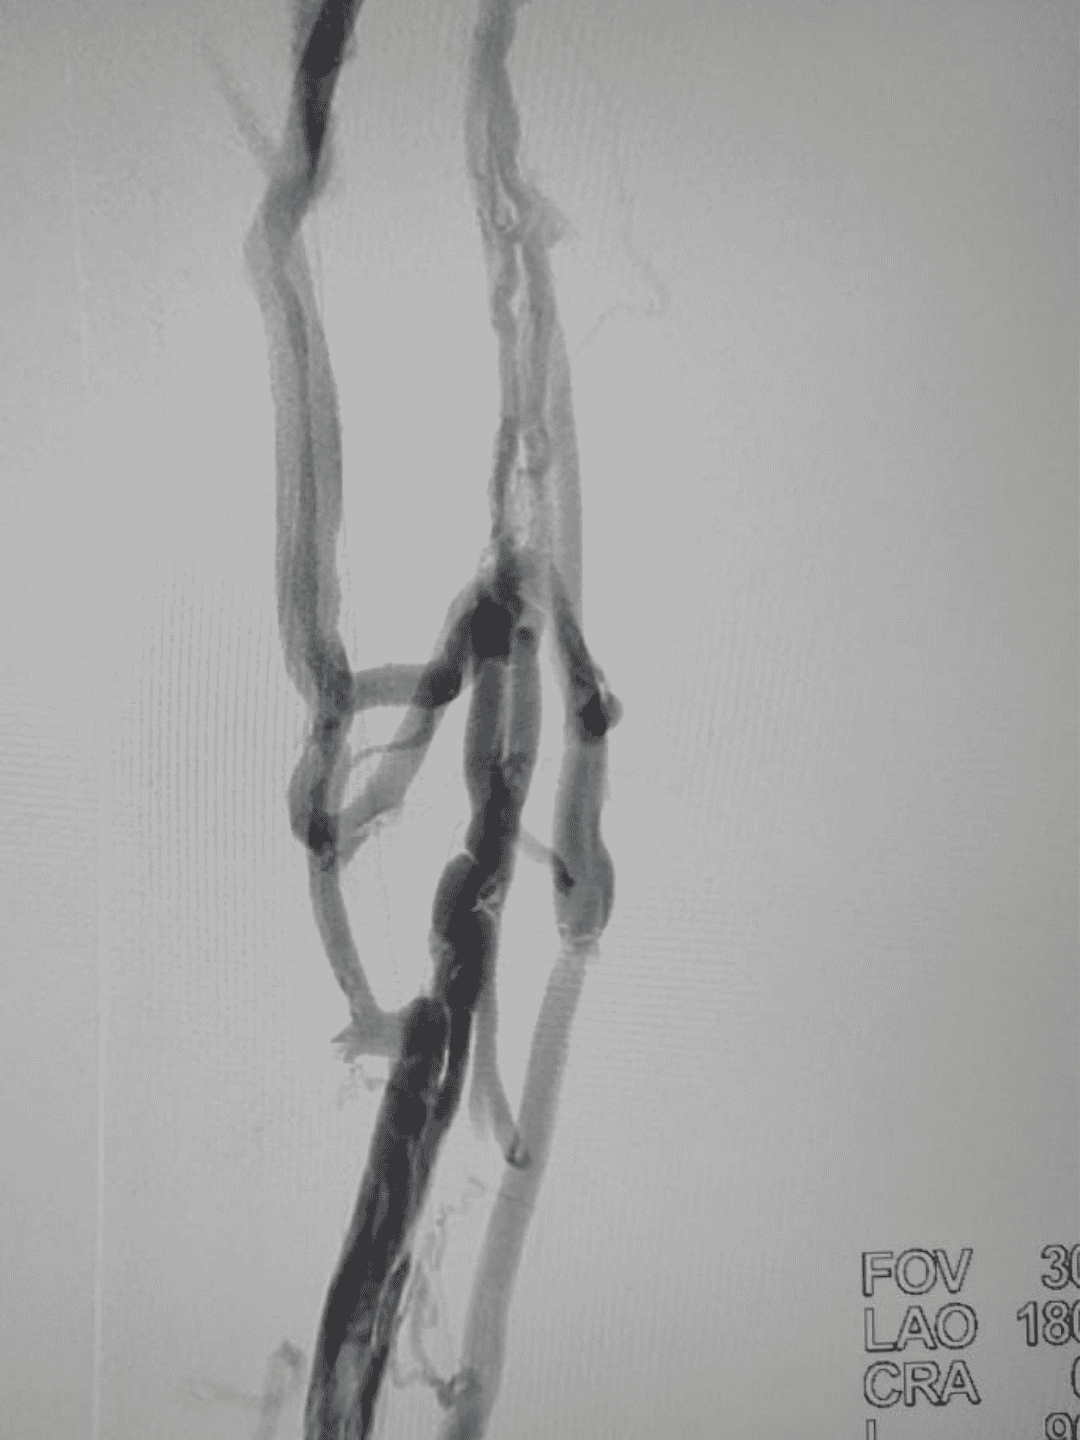

O Sinus Venous é destinado ao tratamento de obstruções sintomáticas das veias femorais e ilíacas, incluindo trombose venosa profunda (TVP) e síndrome pós-trombótica (SPT),/restabelecendo o fluxo em regiões tortuosas do membro inferior e pelve

Trata-se de um stent autoexpansível em nitinol com design híbrido: anéis em célula fechada tipo “Power Diamonds” fornecem alta força radial, conectados por elementos “flash” que conferem excelente flexibilidade, garantindo adaptação eficaz a vasos com curvaturas

Em uma coorte de 200 pacientes, o Sinus Venous apresentou 68% de patência primária, 83% assistida e 90% secundária com seguimento médio de 12 meses. Houve melhora significativa nos escores Villalta, rVCSS e alívio de claudicação venosa